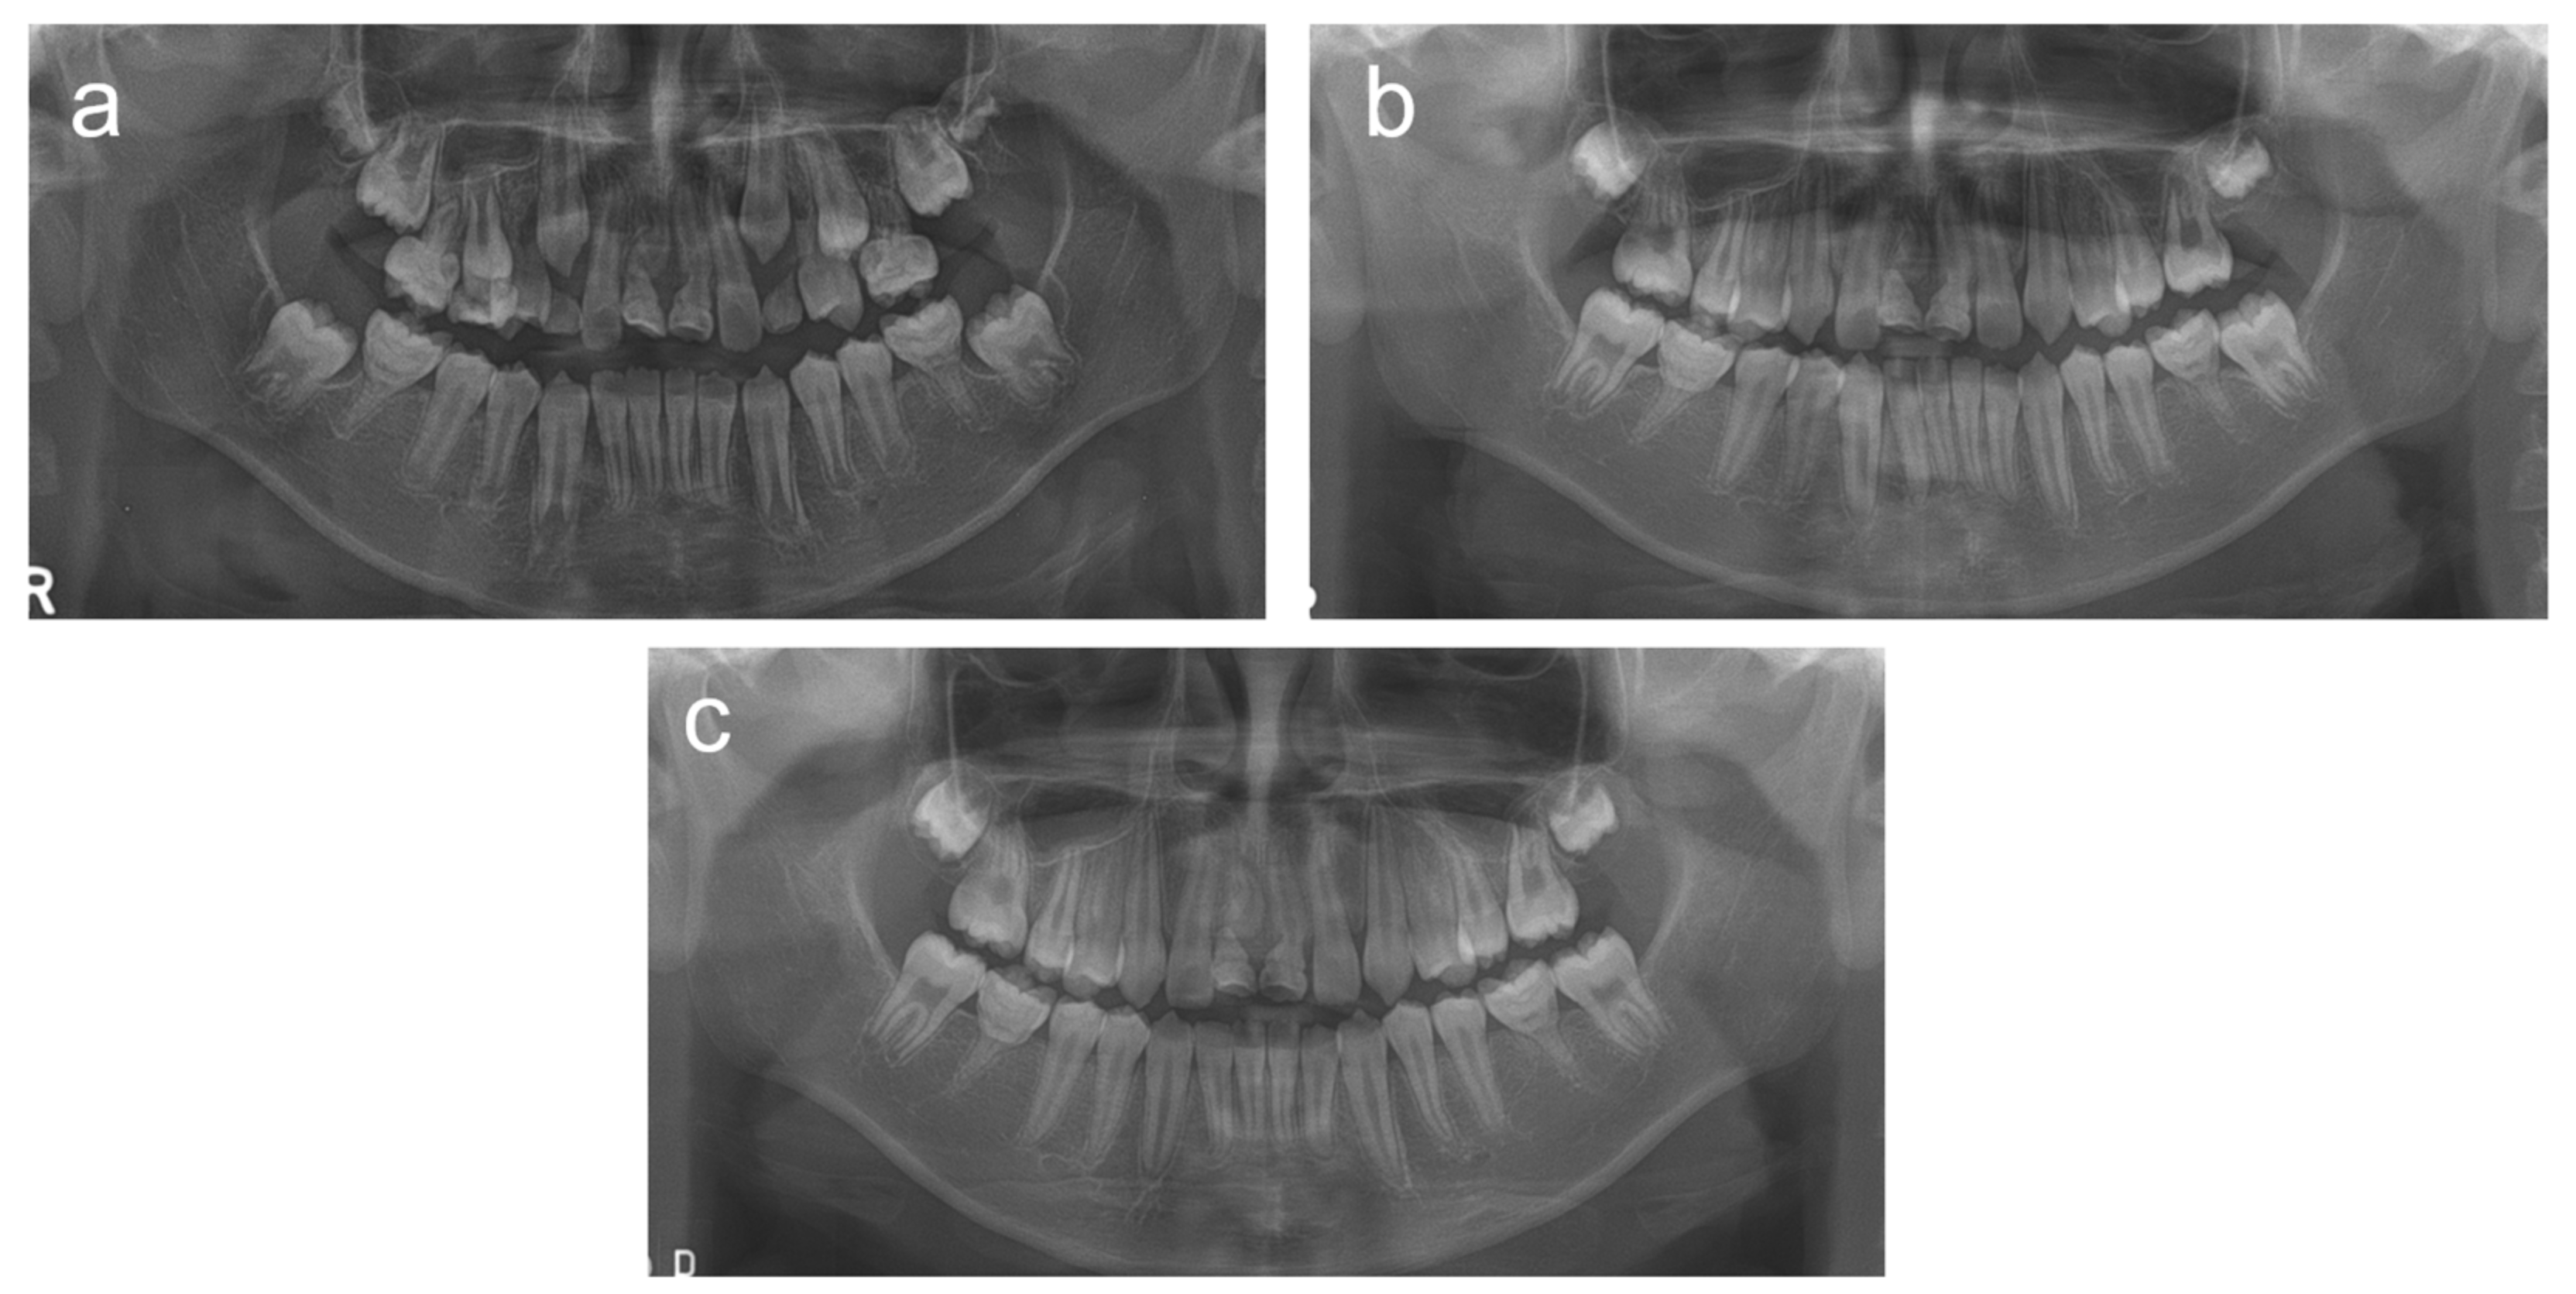

2. Cases

2.1. Case 1

2.2. Case 2

2.3. Case 3

2.4. Case 4

2.5. Case 5